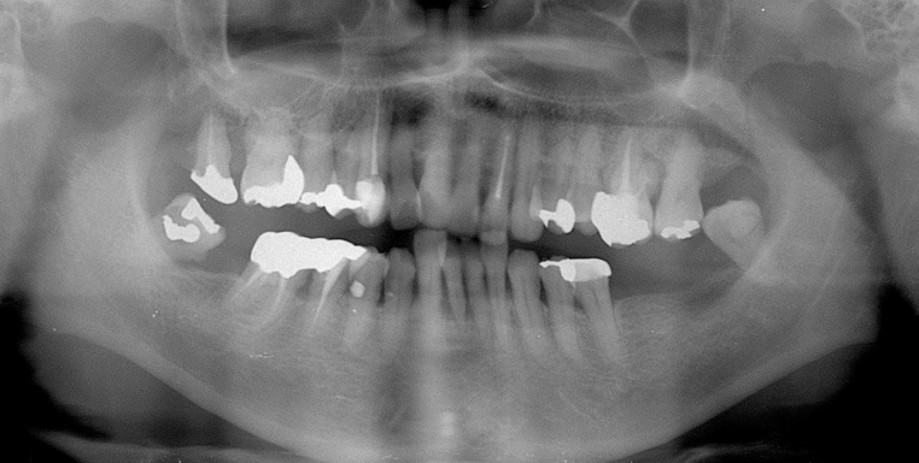

| 主訴 | 60代女性 他院で義歯を作ったが噛みにくい、バネを掛けている左下の銀歯が何度も取れる、しっかり噛めるようになりたい |

| 治療内容 | 歯周病組織再生療法、インプラント治療、セラミック治療を行いました。 |

| 治療費 | 4,000,000円(税込み) |

| 治療期間 | 1年半 |

| 治療回数 | 25回 |

| 想定されたリスク | 失活歯が多く、太くて長い土台がすでに入っていたので、歯根破折のリスクがあった |